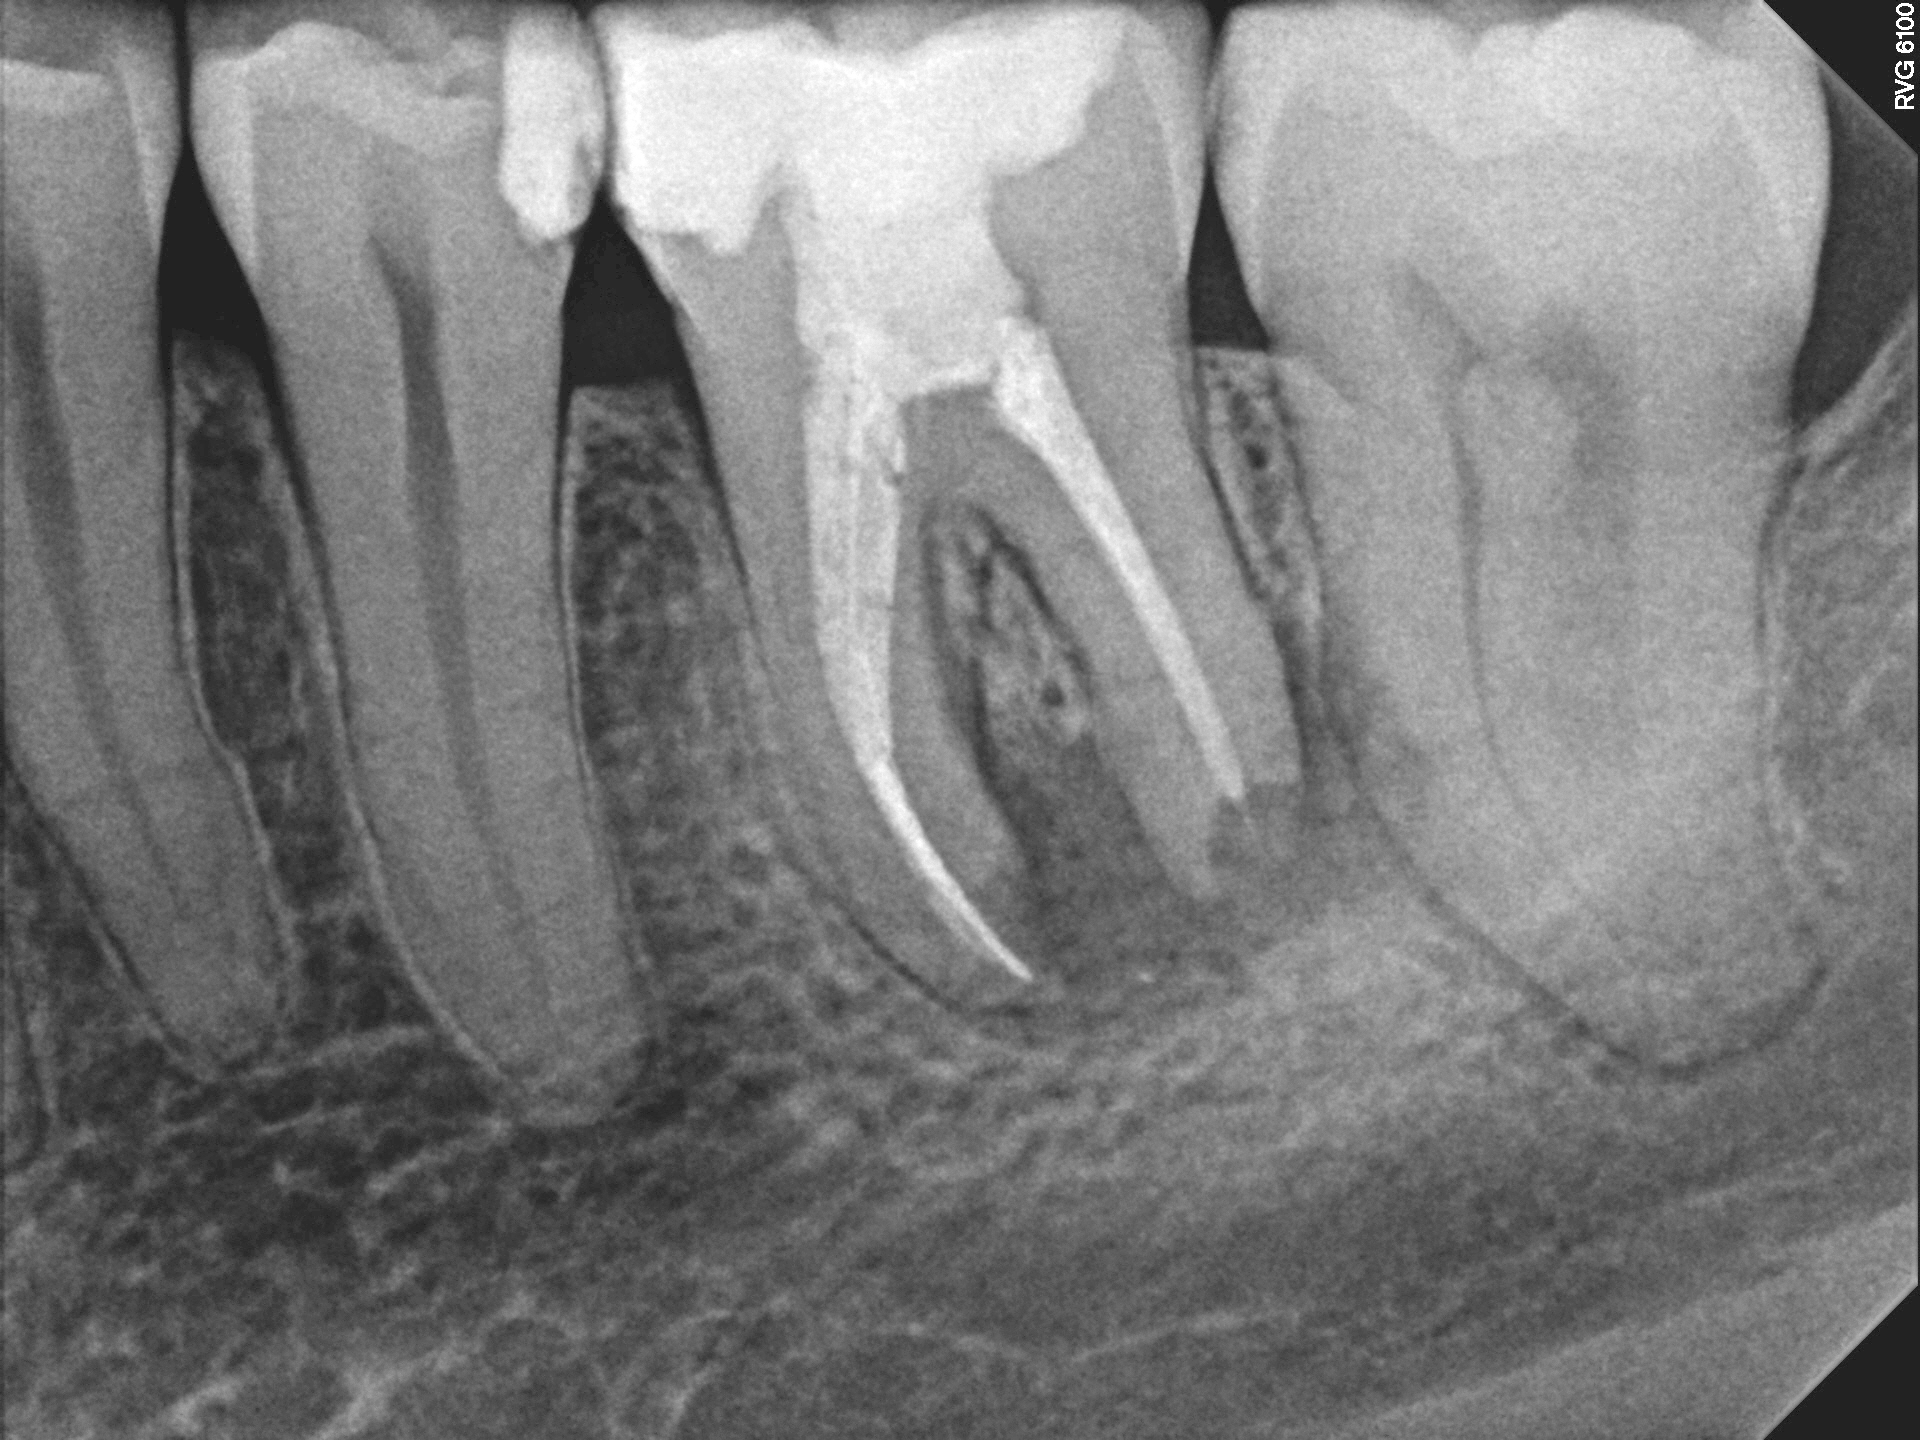

Case 4

A very large infection with a lower molar. The infection extended far from the offending molar and contacts the adjacent teeth. This can lead to the other teeth becoming infected as well, but luckily for this patient, the adjacent teeth were just fine when we started treatment. The right image (one year later) shows the dramatic healing of bone re-growing into the hold in his jaw created by the previous infection. The adjacent teeth remained in good health.